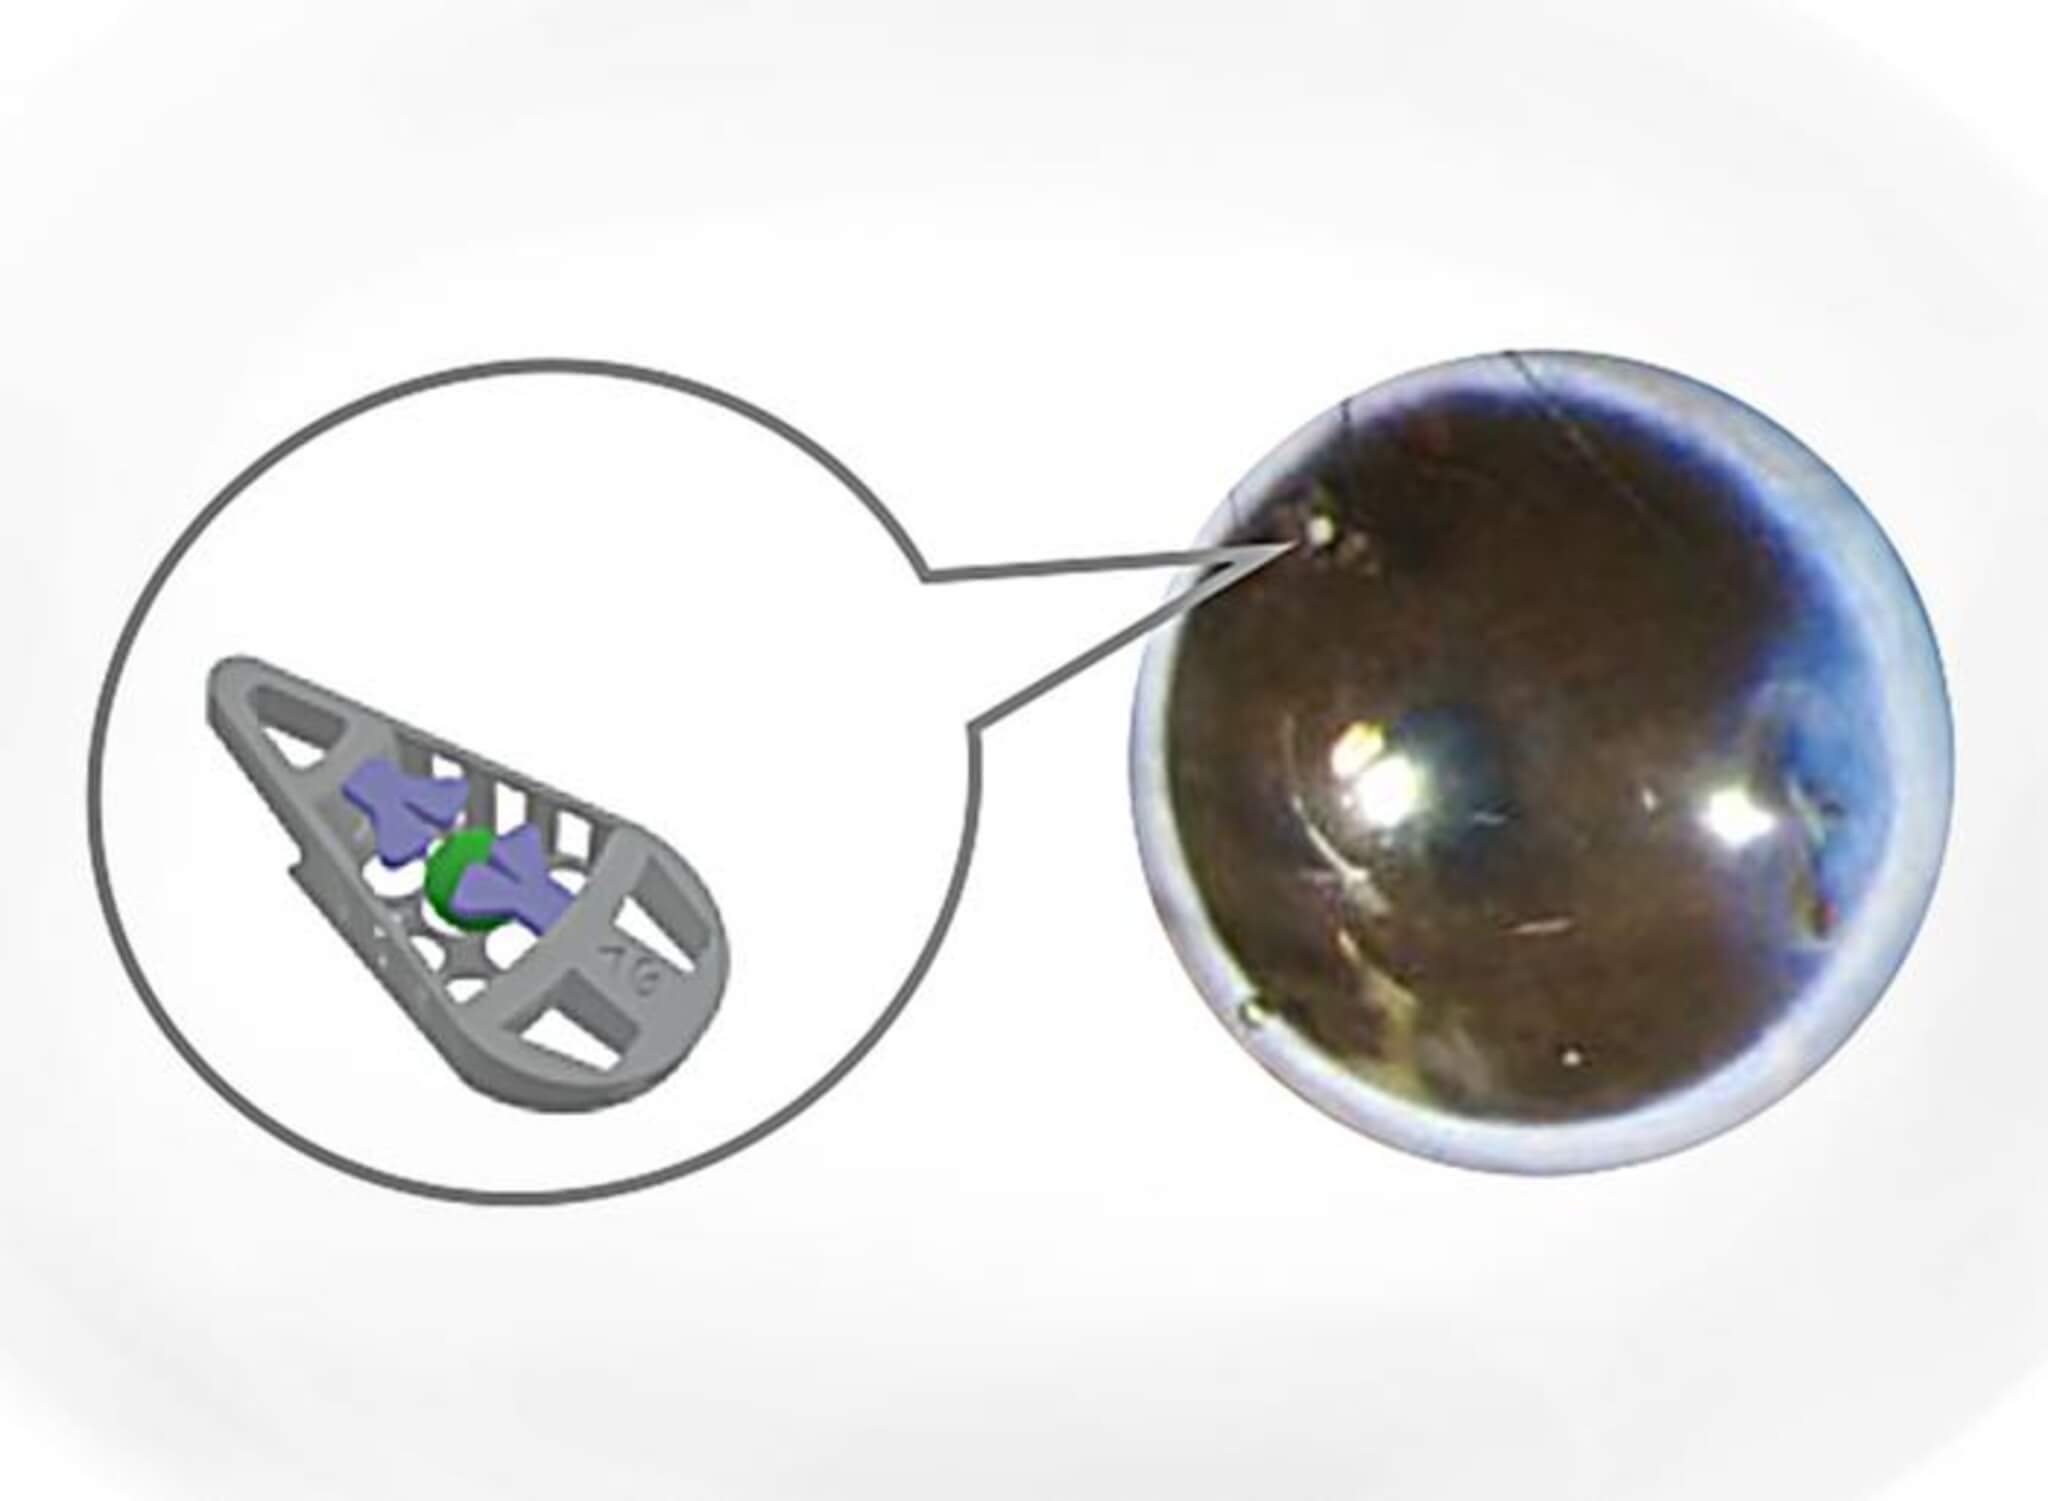

The innovative 3D-printed device, capable of encapsulating insulin-producing pancreatic cells and electronic sensors, was engineered by a team from KTH Royal Institute of Technology and Karolinska Institutet. This collaboration allows for the precise placement of mini-organs, such as pancreatic islets or islets of Langerhans, inside the eye without the need for sutures. This advancement offers exciting prospects for cell-based treatments, particularly for addressing Type 1 or Type 2 diabetes, using the eye as a platform.

The device itself is designed in the shape of a wedge, measuring around 240 micrometers in length. This design allows the structure to be securely positioned in the anterior chamber of the eye (ACE), at the angle between the iris and the cornea. This work marks the first-ever mechanical fixation of a device in the anterior chamber of the eye.

“We designed the medical device to hold living mini-organs in a micro-cage and introduced the use of a flap door technique to avoid the need for additional fixation,” notes Wouter van der Wijngaart, professor in the Division of Micro- and Nanosystems at KTH.

The device’s design ensures that it can position mini-organs, such as organoids and islets of Langerhans, without restricting the supply of nutrients to the cells.